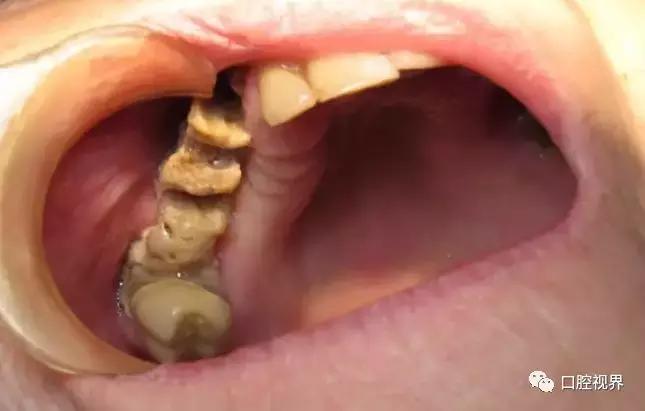

BRONJ的临床表现与放射性颌骨坏死类似,患者可能长期无明显症状,也可表现为颌骨疼痛或骨面裸露。典型的临床表现包括疼痛、骨面裸露、软组织肿胀、感染、牙齿松动、溢脓、瘘管形成。也可见骨面暴露但不伴感染症状的病例。其他症状还包括牙关紧闭、口臭、复发性脓肿、上颌窦炎、口腔上颌窦瘘等。当压迫周围神经时,可出现剧烈的颌骨疼痛或麻木,病情严重者甚至出现病理性骨折。